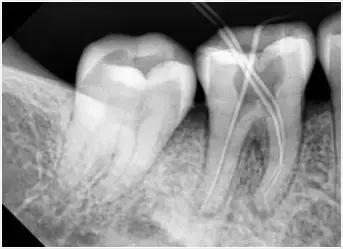

3、确定根管工作长度

应用平行投照X线方法、根管长度测量仪确定根管度,最好插针拍X片。